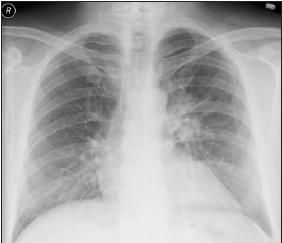

Laboratory test results showed leukocytosis (WBC count of 17,700/μL, with 72% neutrophils and 2.2% eosinophils), hemoglobin level of 12.2 g/dL, and platelet count of 419,000/μL. Results of a basic chemistry panel were normal. A chest radiograph displayed an improved perihilar infiltrate in the left lung (Figure 1).

Figure 1 – A left perihilar infiltrate with enlargement of the left hilum can be seen in this posteroanterior chest radiograph. The patient had fever, malaise, and cough.